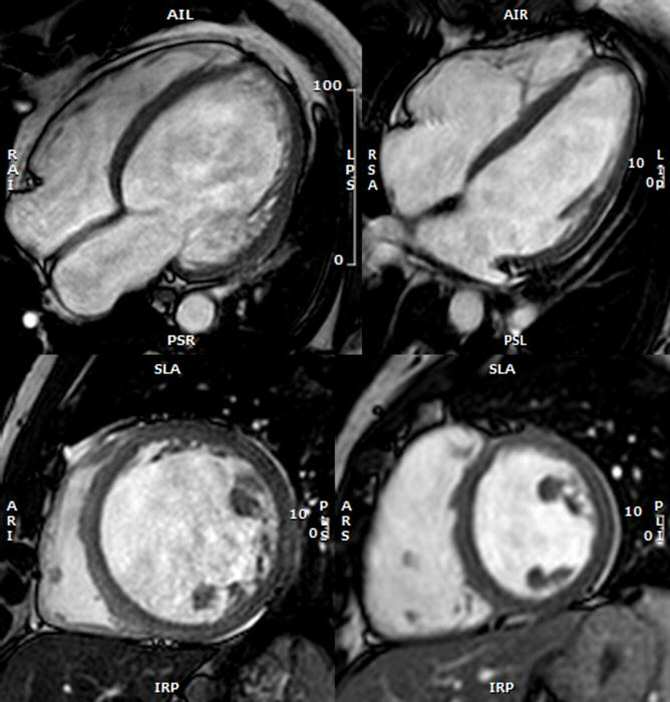

A la izquierda, resonancia magnética de un paciente con miocardiopatía dilatada. A la derecha, resonancia magnética de una persona sin ese problema. En el caso del paciente con miocardiopatía dilatada, el tamaño de su corazón es mayor de lo normal y su capacidad de bombear sangre es menor de lo normal. (Imágenes: CNIC)

Asimismo, añade el Dr. García Pavía, “los pacientes con alteraciones genéticas en genes sarcoméricos o aquellos cuyos corazones presentaban algo de fibrosis en la resonancia magnética tenían más riesgo de desarrollar la cardiopatía”.

Además, destaca el Dr. García Pavía, “hemos identificado que los pacientes que desarrollaron la enfermedad compartían con más frecuencia algunas características concretas como una edad mayor, alteraciones en el electrocardiograma y un corazón con un tamaño mayor y con menos fuerza de bombeo, aunque dentro de lo normal”.